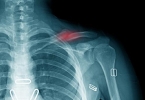

• 锁骨下动脉堵塞是怎么回事

锁骨下动脉堵塞是怎么回事

锁骨下动脉堵塞可能由动脉粥样硬化、大动脉炎、血栓栓塞、先天性血管畸形、外伤等因素引起,可通过药物治疗、血管介入或手术重建等方式治疗。1、动脉粥样硬化长期高血压、高血脂或糖尿病可能导致动脉内膜脂质沉积, ...